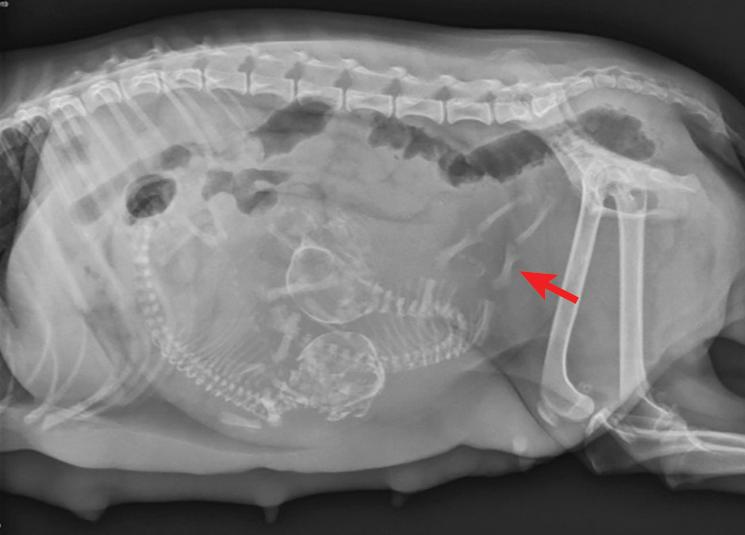

Day 52 of dog pregnancy top, Diagnosing Treating Canine Dystocia Clinician s Brief top

Diagnosing Treating Canine Dystocia Clinician s Brief

Padme s Canine Pregnancy Vlog Day 52 Entry 7 top, My dog is about 51 days pregnant yesterday she started a brown top, LABRADOR RETRIEVER CASSIE 52 DAYS PREGNANT top, How Long Are Dogs Pregnant Labour Gestation Period top, Dog Pregnancy Calendar What To Expect When She s Expecting top, Pregnancy Ultrasound Radiographs Conyers Animal Hospital top, Pregnancy calendar day by day top, Whelping Puppies Unexpected Early Delivery. Raising Puppies top, Week by Week Dog Pregnancy Signs for Proud Puppy Parents top, 38 Days Pregnant Dog 2024 www.gemologytidbits top, Dog Pregnancy Day by Day Timeline Stages and Tests Dog Health Guide top, The Last Week of A Great Dane s Pregnancy Dog Blog It top, My dog is showing all signs of pregnancy but xray showed no top, Canine Pregnancy Calculator and Calendar top, 12 Signs of False Pregnancy in Dogs PetHelpful top, How Long Are Dogs Pregnant Dog Gestation Period top, How Long Are Dogs Pregnant Dog Gestation Period Explained top, Abortion top, D Litter Diary top, Veterinary Sciences Free Full Text Development of Dog Immune top, Diagnosing Treating Canine Dystocia Clinician s Brief top, Canine Pregnancy Scanning West Midlands top, D Litter Diary top, French Bulldog Pregnancy Stages 9 Weeks Of Fun French Bulldog top, Dog Pregnancy Calendar Find Out When Your Canine Is Due To Deliver top, Canine Pregnancy Calendar top, Early Contractions and Labor top, Pregnancy in Dogs Dog News top, Dog Pregnancy Stages Revival Animal Health Learn More top, My dog is showing all signs of pregnancy but xray showed no top, Canine pregnancy diagnosis PPT top, How Long Are Dogs Pregnant Dog Gestation Period top, Welping box is complete 52 days pregnant westbygodvirginiacanecorso gooddogbreeder akccanecorso canecorsopuppies embark top, 5 Ways to Care for a Pregnant Dog wikiHow top, Dog Pregnancy Day by Day Timeline Stages and Tests Dog Health Guide top.

Padme s Canine Pregnancy Vlog Day 52 Entry 7 top, My dog is about 51 days pregnant yesterday she started a brown top, LABRADOR RETRIEVER CASSIE 52 DAYS PREGNANT top, How Long Are Dogs Pregnant Labour Gestation Period top, Dog Pregnancy Calendar What To Expect When She s Expecting top, Pregnancy Ultrasound Radiographs Conyers Animal Hospital top, Pregnancy calendar day by day top, Whelping Puppies Unexpected Early Delivery. Raising Puppies top, Week by Week Dog Pregnancy Signs for Proud Puppy Parents top, 38 Days Pregnant Dog 2024 www.gemologytidbits top, Dog Pregnancy Day by Day Timeline Stages and Tests Dog Health Guide top, The Last Week of A Great Dane s Pregnancy Dog Blog It top, My dog is showing all signs of pregnancy but xray showed no top, Canine Pregnancy Calculator and Calendar top, 12 Signs of False Pregnancy in Dogs PetHelpful top, How Long Are Dogs Pregnant Dog Gestation Period top, How Long Are Dogs Pregnant Dog Gestation Period Explained top, Abortion top, D Litter Diary top, Veterinary Sciences Free Full Text Development of Dog Immune top, Diagnosing Treating Canine Dystocia Clinician s Brief top, Canine Pregnancy Scanning West Midlands top, D Litter Diary top, French Bulldog Pregnancy Stages 9 Weeks Of Fun French Bulldog top, Dog Pregnancy Calendar Find Out When Your Canine Is Due To Deliver top, Canine Pregnancy Calendar top, Early Contractions and Labor top, Pregnancy in Dogs Dog News top, Dog Pregnancy Stages Revival Animal Health Learn More top, My dog is showing all signs of pregnancy but xray showed no top, Canine pregnancy diagnosis PPT top, How Long Are Dogs Pregnant Dog Gestation Period top, Welping box is complete 52 days pregnant westbygodvirginiacanecorso gooddogbreeder akccanecorso canecorsopuppies embark top, 5 Ways to Care for a Pregnant Dog wikiHow top, Dog Pregnancy Day by Day Timeline Stages and Tests Dog Health Guide top.